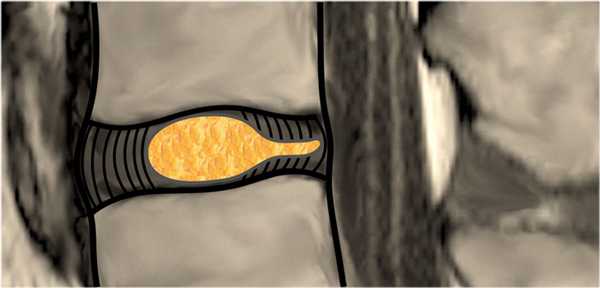

Грыжа диска - смещение диска за пределы границы межпозвонкового пространства.

Протрузия: ширина между краями грыжи диска, меньше ширины у основания грыжи.

Экструзия: ширина между краями грыжи диска, больше ширины у основания грыжи.